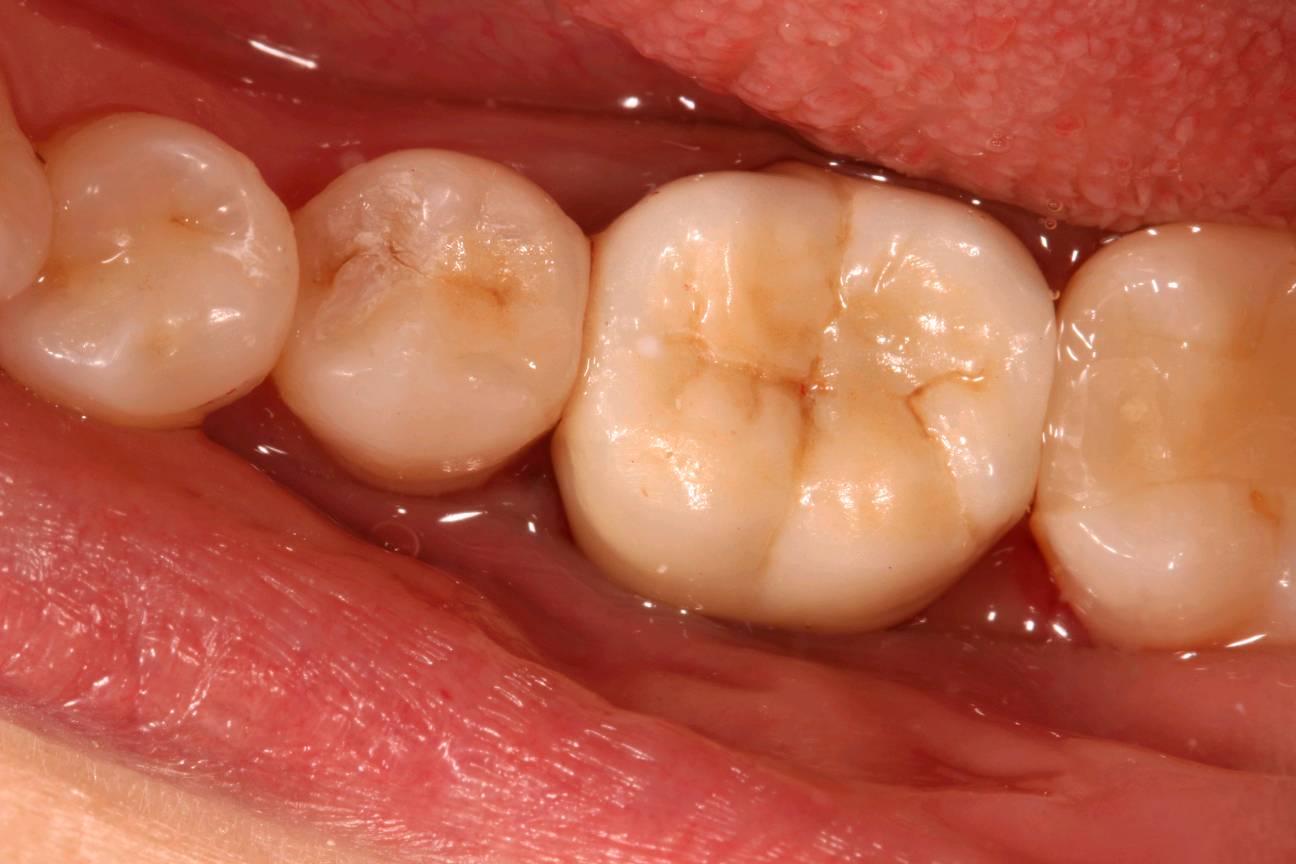

基牙预备,排龈,精修,瓷睿刻扫描,比色。

图片发自160App